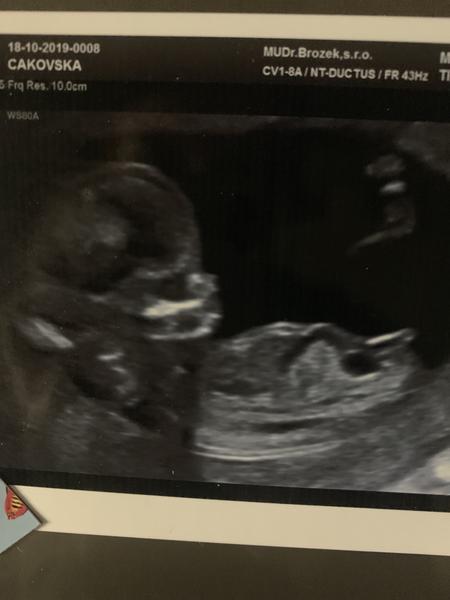

@lilian2111 Jestli chcete mužu vám poslat vysledky nt+